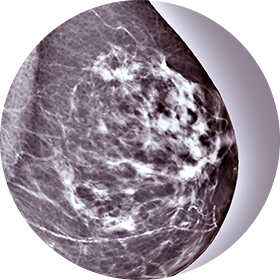

유방촬영술

유방암 검진의 가장 기본적인 검사로 비교적

간단하게 시행할 수 있는 검사입니다. -